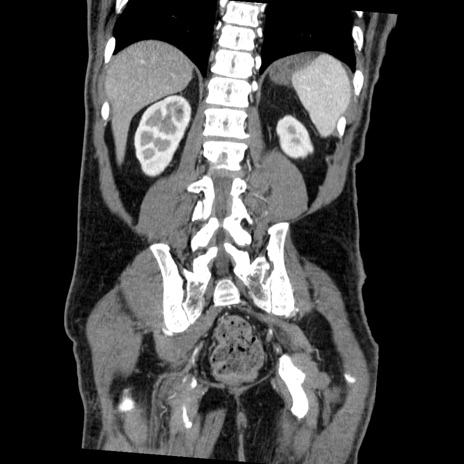

症例22(冠状断像)

【症例】50歳代男性

【主訴】腹痛

【現病歴】AVMからの被殻出血のため回復期リハ病棟入院中。 本日午後3時頃急に下腹部痛が出現した。

【既往歴】AVM、被殻出血、虫垂炎、高血圧

【身体所見】意識晴明、左半身不全麻痺、会話の理解は良好、36.5°C、腹部:膨隆、全体に板状硬、下腹部正中に圧痛点あり、反跳痛-、筋性防御不明、右下腹部にope scar

【データ】WBC 9400、CRP 0.06